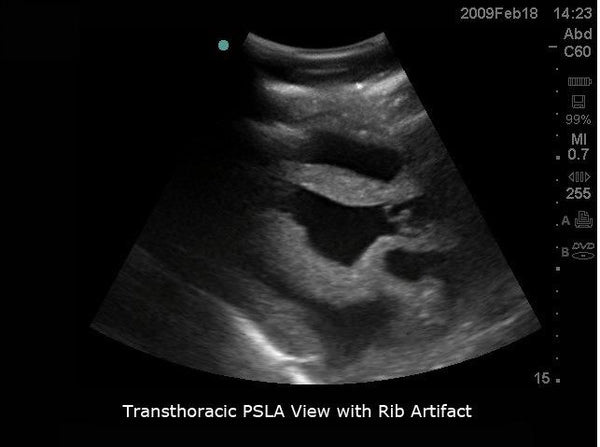

健康+医学 Transesophageal Echocardiography Transesophageal Echocardiogram (TEE)の詳細情報

Transesophageal Echocardiogram (TEE)。Transesophageal Echocardiography-Guided Extracorporeal。Transesophageal Echocardiography in Critical Care | Current。

The role of transesophageal echocardiography in clinical use

題名:PracticalApproachtoTransesophagealEchocardiography,4thed.

著者:A.C.PerrinoJr.&S.T.Reeves(eds.)

出版社:WOLTERSKLUWER

ISBN:978-1-4963-8347-1

ページ数:643pp.

出版年:2020年

定価24,739円(本体22,490円+税)